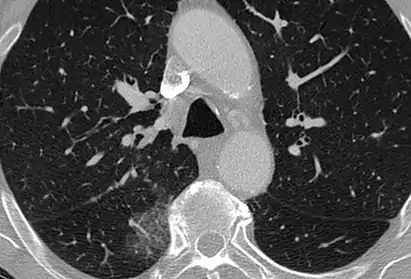

CT showing diffuse ground-glass opacities in periphery of both lungs in patient with COVID-19.